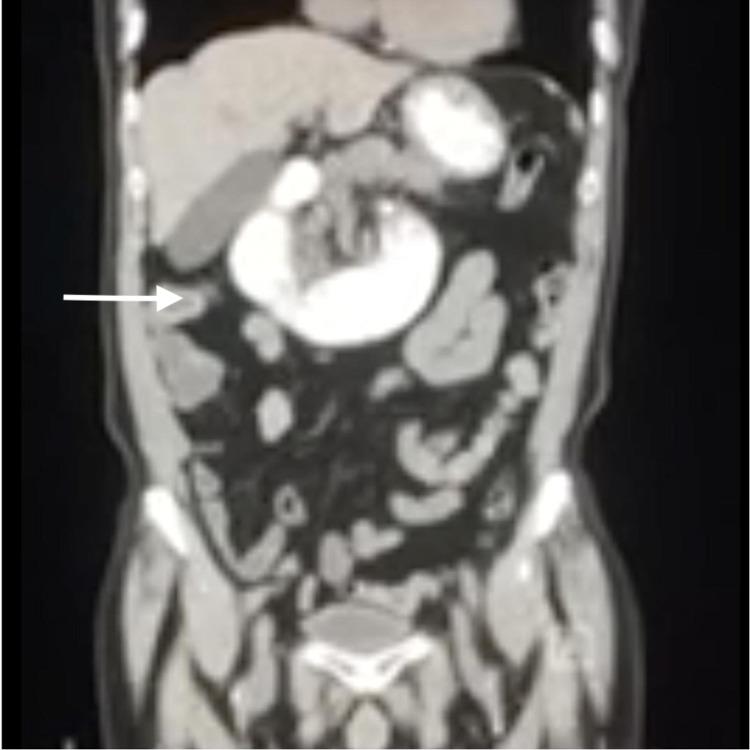

Signet ring cell carcinoma (SRCC) is an uncommon and poorly differentiated tumor. It arises mostly in the gastrointestinal tract. The incidence of gastric SRCC has increased in the past few years. Volvulus is the twisting of the bowel around its mesentery. It is classified as either primary or secondary. It is relatively common in the cecum and sigmoid colon. Volvulus of other parts of the gastrointestinal tract is relatively rare. Herein, we present a case of small bowel volvulus (SBV) secondary to advanced gastric SRCC with peritoneal carcinomatosis. The patient had presented with nausea and vomiting. Initial computed tomography (CT) scan of abdomen unveiled jejunal volvulus. SBV resolved spontaneously on a repeat CT scan. Enteroscopy with histopathology confirmed the diagnosis of gastric SRCC, which turned to be metastatic to peritoneum on laparoscopy. We believe our case is unique due to the rarity of advanced gastric SRCC presenting as secondary jejunal SBV without appreciated gastric mass on imaging.

印戒细胞癌(SRCC)是一种罕见且分化程度低的肿瘤。它主要发生在胃肠道。在过去几年中,胃SRCC的发病率有所上升。肠扭转是指肠管围绕其系膜扭转。它分为原发性或继发性。在盲肠和乙状结肠中相对常见。胃肠道其他部位的肠扭转相对少见。在此,我们报告一例继发于晚期胃SRCC伴腹膜转移癌的小肠扭转(SBV)病例。患者表现为恶心和呕吐。腹部初次计算机断层扫描(CT)显示空肠扭转。重复CT扫描时SBV自行缓解。经肠镜检查及组织病理学检查确诊为胃SRCC,腹腔镜检查显示已转移至腹膜。我们认为我们的病例很独特,因为晚期胃SRCC表现为继发性空肠SBV且影像学上未发现胃部肿块的情况很罕见。